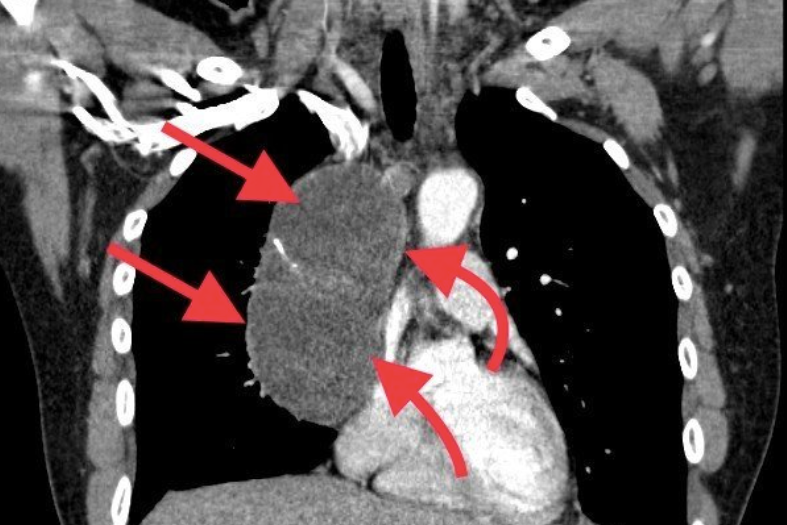

Bệnh nhân tên M.T.S, ở Định Hóa, Thái Nguyên, nhập viện trung tuần tháng 4. Kết quả hội chẩn liên khoa, bác sĩ đưa ra kết luận chẩn đoán u trung thất. Khối u trong lồng ngực lớn, đã có biến chứng chèn ép vào tim, phổi và mạch máu, có nguy cơ ảnh hưởng đến tính mạng người bệnh.

Tiến sĩ Lô Quang Nhật, Trưởng khoa Ngoại tim mạch - Lồng ngực, Bệnh viện Trung ương Thái Nguyên, cho biết bệnh nhân được mổ nội soi lồng ngực, cắt bỏ khối u kích thước lớn (13 x 8 x 7cm).